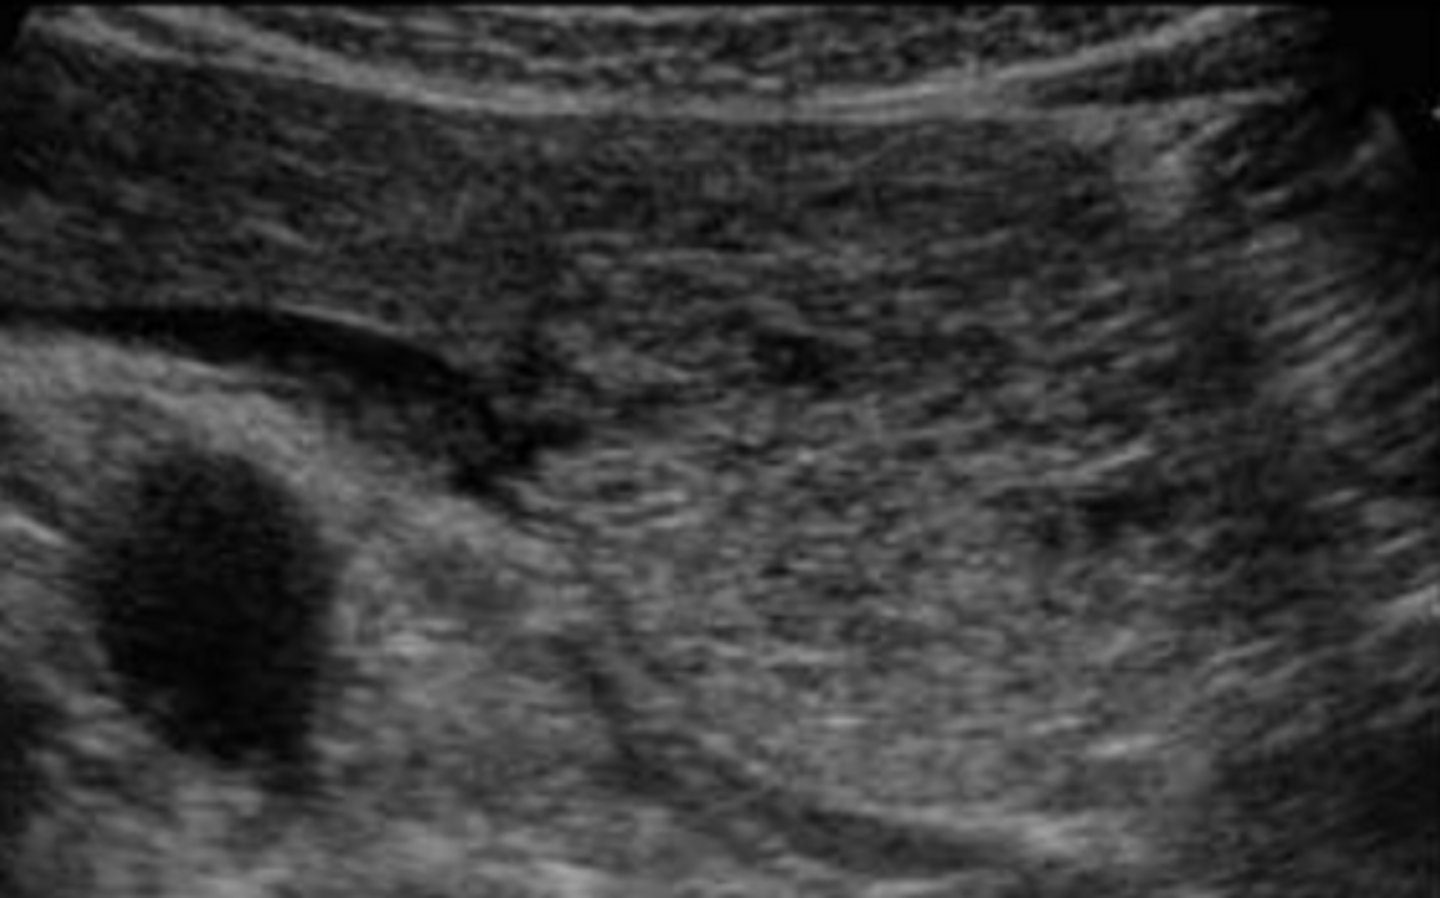

Islet Cell Tumor (Adenoma) Sonographic Appearance

-generally homogenous and solid

-frequently hypoechoic

-larger tumors may become moderatly echogenic

-calcifications and fluid areas seen in larger lesions

-solid masses are generally functional while those w/ cystic areas of necrosis are generally non functional

-small 1-2cm tumors difficult to identify

Islet Cell Tumor (Adenoma)